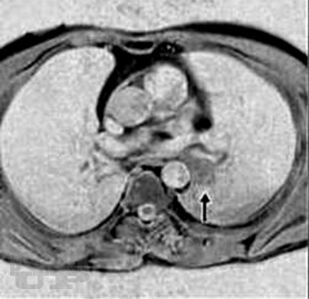

Представлено современное состояние проблемы различных форм злокачественных опухолей бронхолегочной системы, включая и паранеопластические проявления рака легкого. Представлены этиопатогенетические аспекты развития раковой болезни. Даны современные классификации рака легкого. Клиническая картина изложена систематизированно, с алгоритмом дифференциально-диагностического аспекта. Отражены последние достижения и перспективные исследования в диагностике рака легкого. Особое внимание уделено современным методам лечения рака легкого, показаниям и противопоказаниям к применению тех или иных методов лечения, особенно хирургического. Материал сопровождается подробными иллюстрациями.